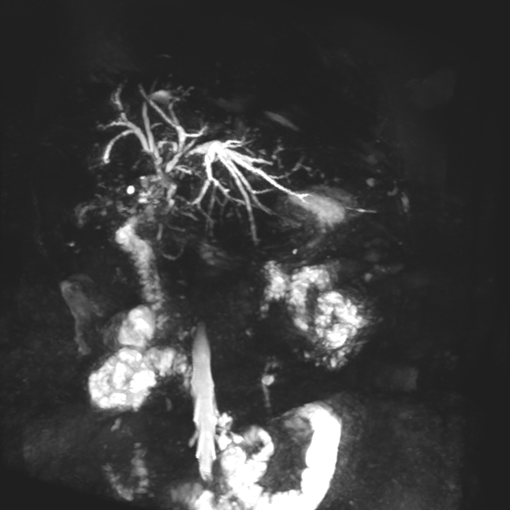

Se observa dilatación de las vías intra hepáticas a expensas de sus ramas hepáticas derecha, anterior y posterior, hepática izquierda y hepática común. El hepático común da la apariencia de estar anastomosado a un asa de intestino, lo que sugiere la posibilidad de una cirugía entero biliar.

No se logra observar el colédoco.

1. Dilatación de vías biliares intrahepáticas

2. Anastomosis entero biliar

3. Colangitis aguda